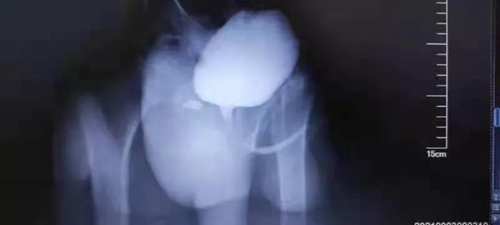

入院后,泌尿外科團(tuán)隊(duì)進(jìn)一步檢查發(fā)現(xiàn)小明體內(nèi)有一個(gè)1.4cm左右大小的前列腺處腫物。成年人尿道和輸尿管的平均直徑在6毫米左右,兒童的則更為狹窄,小明的尿道被腫物“掐住了脖子”,導(dǎo)致排尿非常困難。

CT顯示,在孩子本就狹小的膀胱和直腸間隙中尋找直徑僅1.4cm的腫物,難度非常大。這塊“攔路石”究竟該怎么掏?

手術(shù)如期進(jìn)行,團(tuán)隊(duì)成員使用膀胱鏡聯(lián)合腹腔鏡進(jìn)行探查。通過肚臍上開的小孔,手術(shù)醫(yī)生操作腹腔鏡繞過懸吊的膀胱進(jìn)入盆腔,穿過膀胱和直腸狹小的間隙,避開輸精管和尿道,經(jīng)過約2個(gè)小時(shí)的層層分離,終于在緊挨前列腺和精阜相通處找到了“攔路石”,經(jīng)過專家們?cè)\斷確定為前列腺囊腫。手術(shù)醫(yī)生立刻使用超聲刀切除腫物,解決了這塊掐住尿道的“攔路石”。目前,小明身體恢復(fù)良好,已經(jīng)康復(fù)出院。